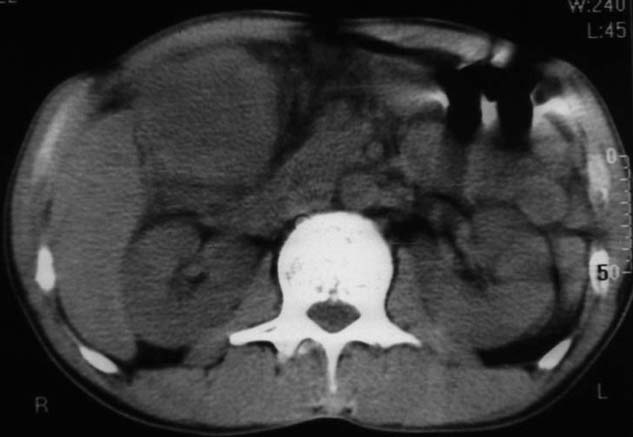

男,50y,右上腹包块痛10天,查:右上腹饱满,右肋下触及6*6cm大小包块,质硬,压痛。患者诉:10天前感冒胸闷,痛,后痛及右上腹部,既往有肝炎病史。

没有增强!只能考虑左叶内侧段巨块型肝癌(外生型)可能性大;胆囊呢?不除外胆囊癌累及肝脏。

病变位于胆囊窝内,其内密度不均,肝总管及胆总管扩张,胃里面没有清水充盈,不解为什么楼主不做好了准备再做呢,支持:“左叶内侧段巨块型肝癌(外生型)可能性大;不除外胆囊癌累及肝脏”建议增强吧。

考虑:肝左内叶巨块型癌,主动脉旁淋巴结转移.(有一层面似见胆囊受压.)